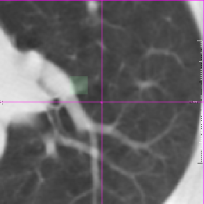

with 𝒙Fsubscript𝒙𝐹\bm{x}_{F} and 𝒙Msubscript𝒙𝑀\bm{x}_{M} the corresponding landmark locations. Based on the idea that the registration error is smooth, we include voxels from a small local neighborhood around the landmarks to increase the total set of available landmarks. In this small neighborhood we assume that the registration error is equal to the error at the center of the neighborhood. This assumption seems reasonable for smooth transformations and within a small region. The neighborhood size is chosen as 10×10×7.5mm10107.5mm10\times 10\times 7.5\;\mathrm{mm}, which is approximately equivalent to the final grid spacing of the B-spline registration (see Fig. 5).

Refer to caption

() Ground truth

(a) Predicted error

(b) Magnification of (a)

(c) Magnification of (b)

Figure 5: Example data from the SPREAD dataset. The left column (a,c) shows the fixed image with the ground truth registration error overlaid in color. The square boxes around each landmark are given the same error as the error at the landmark. The right column (b,d) shows the moving image after registration with the registration error predicted by the proposed method overlaid in color. (c) and (d) are zoomed in versions of (a) and (b).